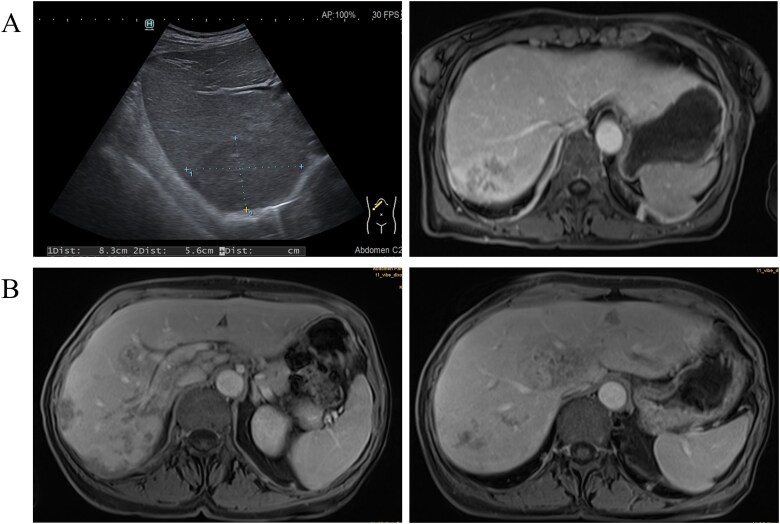

Fascioliasis acquired in Central Asia.